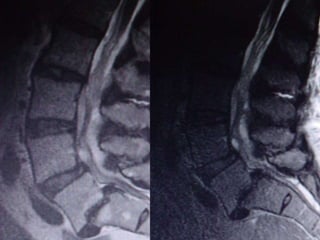

75 wm severe! LBP S/P cement 6 months ago

65 year old man with

Recurrent LBP that is

severe